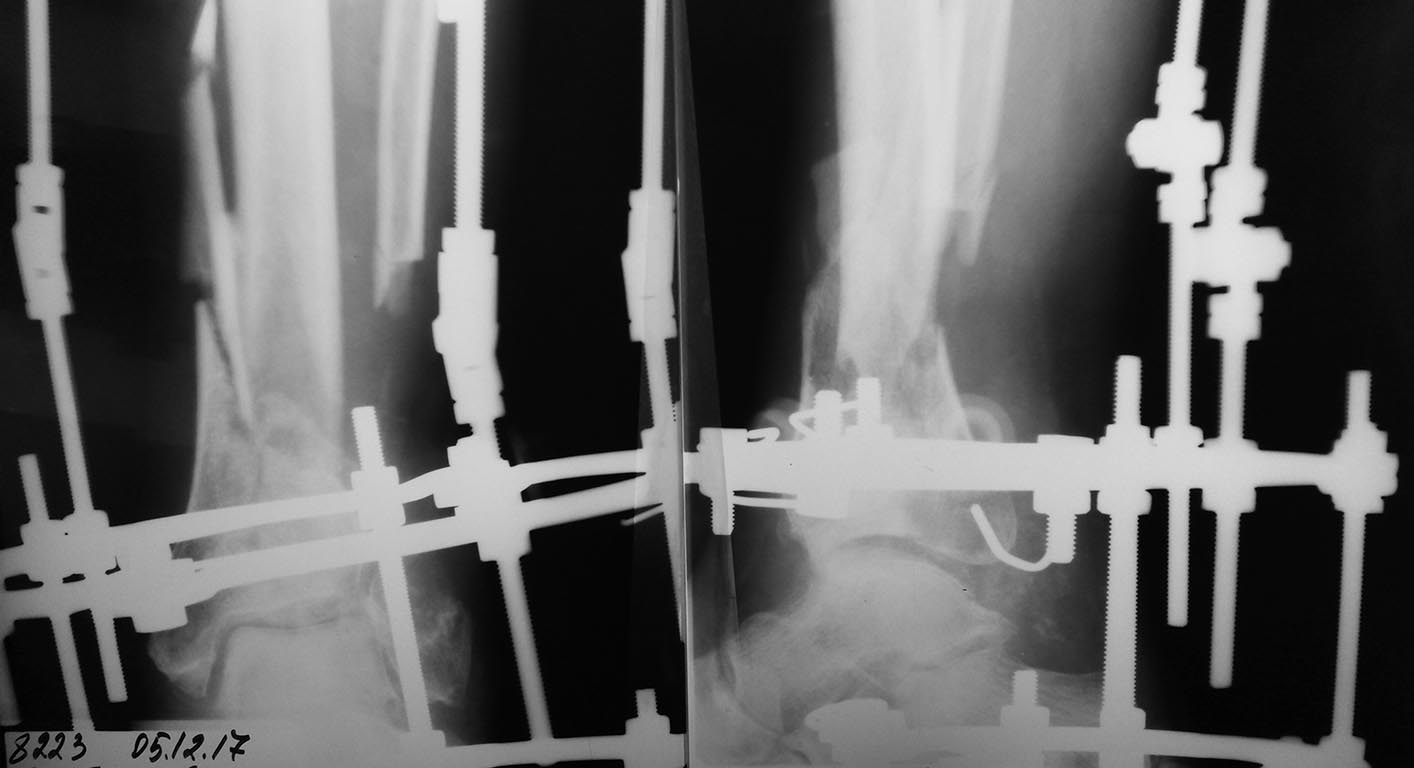

Пациент Г.75, О.оскольчатый перелом обеих костей левой голени,

(упал с дерева высоты более 4м), рана по задне-наружной поверхности.

При поступлении ПХО О.перелома с остеосинтезом АНФ, рана зажила через 3,5 мес.после неоднократных ХО, кожной пластики расщепленным лоскутом и резекции малоберцовой кости. последние рентгенограммы в процессе исправления оси б\б кости в аппарате Илизарова.

Учитывая возраст пациента, избыточную массу тела,отсутствие латеральной опоры (м/б кость) , есть ли смысл бороться за голеностоп? может быть лучше провести артродез интрамедулярным штифтом? и каким именно?